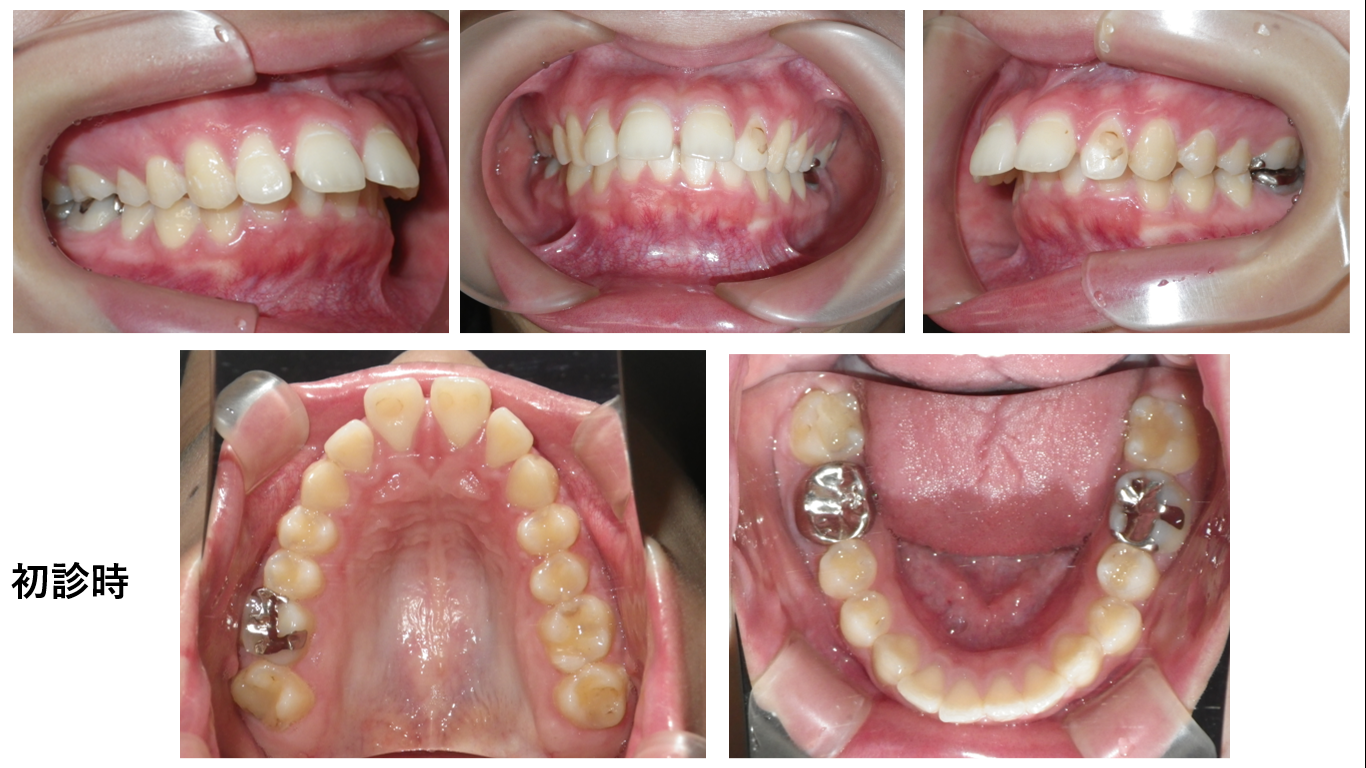

矯正症例142 AngleⅠ級、上顎前突

初診時24歳、性別:女性、治療期間2年8か月、抜歯部位:上顎左右5番、下顎左右4番,治療費総額1,030,000円(税込み)この症例も患者さんから症例掲載の許可を得ています。 抜歯するかしないかで悩ん...